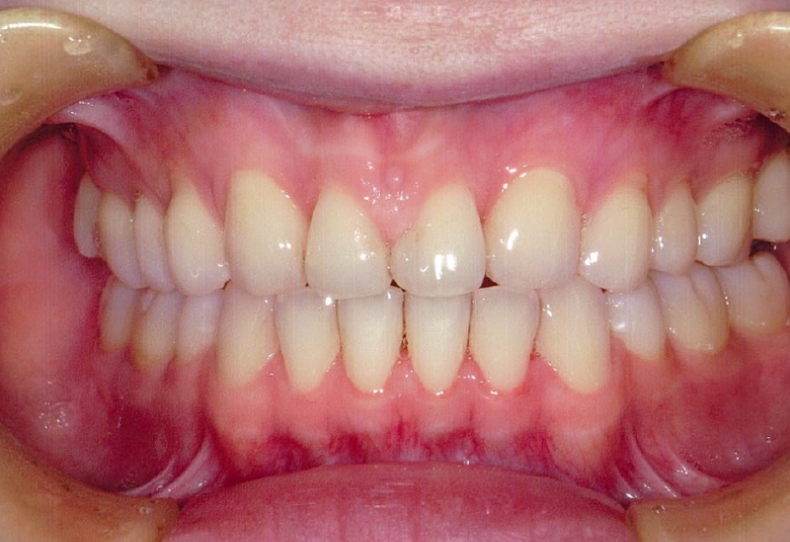

治療後